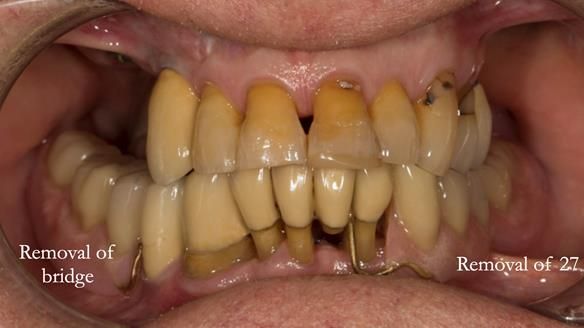

In the upper arch:

- a failing upper left tooth supporting a bridge was removed

- an implant-supported bridge on the upper right was dismantled

A metal-based upper RPD was made,

with metal backings incorporated to future-proof the design

should further teeth fail.